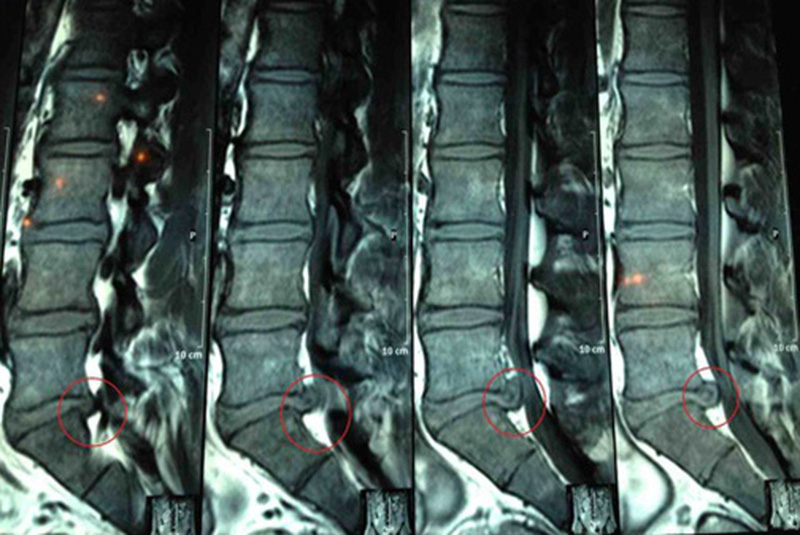

Chụp cộng hưởng từ (MRI): Một từ trường được sử dụng để tạo ra hình ảnh của cơ thể. Thủ tục này có thể được sử dụng để xác nhận vị trí của đĩa đệm thoát vị và để kiểm tra ảnh hưởng đến dây thần kinh.

Vi tính cắt lớp (CT scan): X - quang tạo ra hình ảnh cắt ngang của cột sống và các cấu trúc xung quanh nó.

Myelogram: Một chất nhuộm màu được tiêm vào dịch tủy sống, và sau đó X quang được chụp. Thử nghiệm này có thể hiển thị áp lực lên cột sống hoặc dây thần kinh do thoát vị đĩa đệm hoặc các vấn đề khác.

X quang: Bằng X quang không phát hiện được ổ thoát vị đĩa đệm, nhưng có thể được thực hiện để loại trừ nguyên nhân khác gây đau lưng, chẳng hạn như nhiễm trùng, khối u hoặc xương bị gãy.